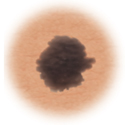

Atypical moles (dysplastic nevi)

Larger than normal moles (more than a half inch across), atypical moles are not always round. Atypical moles can be tan to dark brown, on a pink background. These types of moles may occur anywhere on the body.

Treatment may include removal of any atypical mole that changes in color, shape, or diameter. In addition, people with atypical moles should avoid sun exposure, since sunlight may accelerate changes in atypical moles. People with atypical moles should see a healthcare provider for any changes that may indicate skin cancer.